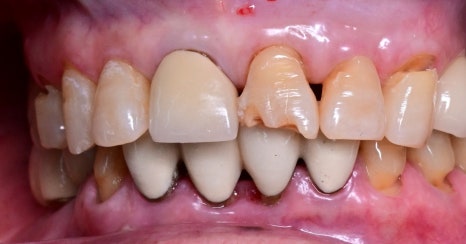

오른쪽 사진: 환자분의 앞니 구강 내 사진입니다.

앞니는 깨지고 오래된 보철물도 있어, 심미성과 기능 회복이 함께 필요한 상태였습니다.